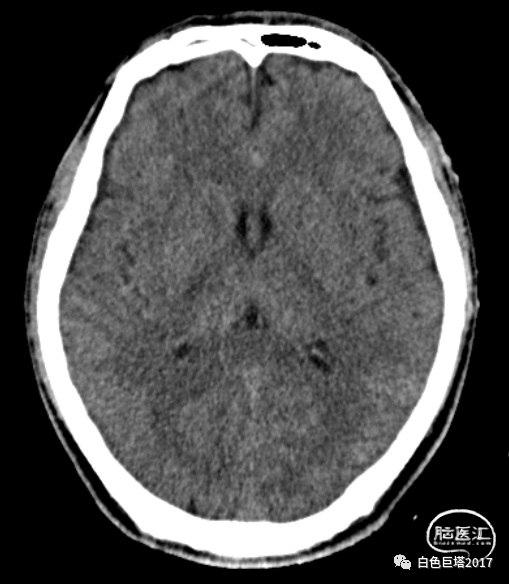

患者苏某,34岁男性,因“高处坠落致意识障碍1小时余”入院。患者自8米高处坠落,头面部着地,入院时头面创口、口腔、鼻腔流血不止,GCS E2V1M5为8分。很快出现血压下降至70/52mmHg、血氧下降85%。急诊气管插管,完善头颅、颈椎、胸腹部CT检查,提示颌面、颅底多发骨折、鼻腔积血,软组织挫裂伤,左颞颌关节脱位,牙齿缺失。额骨骨折、右额顶叶脑挫裂伤、蛛网膜下腔出血,颅内积气。颈椎间盘突出、颈椎退行性变、未见明显骨折。双侧1-2肋骨骨折,T5-7左侧横突骨折;双肺挫伤;左侧少量气胸。腹腔脏器未见明显损伤表现。